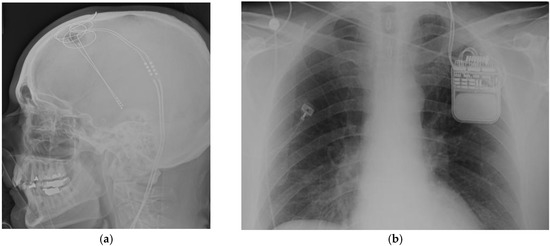

Figure 2.

(a) Frame based system for deep brain stimulation; (b) Frameless bases system for deep brain stimulation.